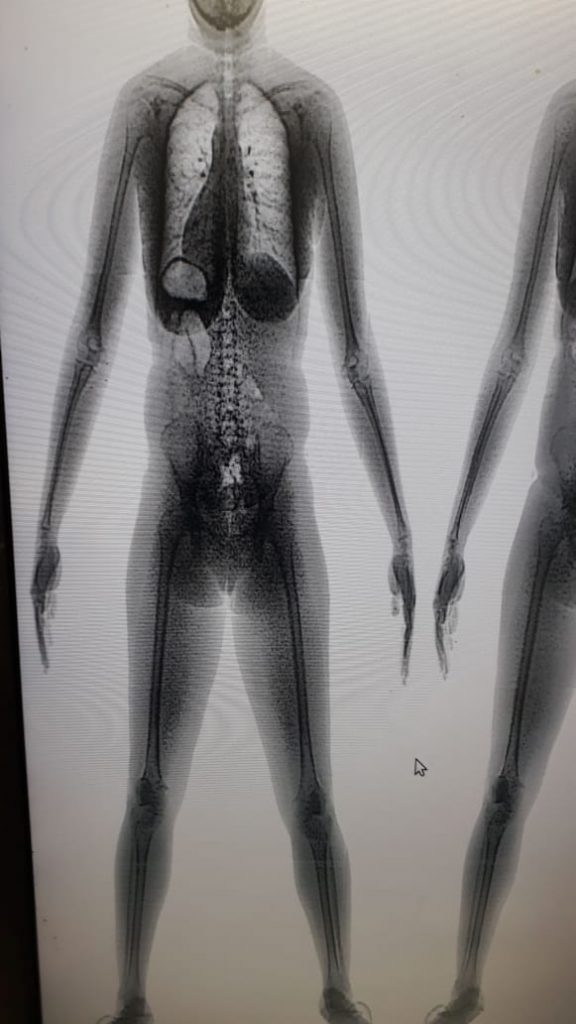

O coronel Reinaldo Chaves, secretário-executivo da Sejuc, explicou que, com a implementação do body scan, as revistas passaram a ser realizadas de forma totalmente digital sem a exposição dos visitantes a situações como a retirada de vestimentas. “O estado de Sergipe, desde o ano de 2017, com a aquisição dos aparelhos de body scan, aboliu qualquer tipo de revista vexatória. O scanner corporal é de alta tecnologia e consegue detectar a substância no interior do corpo humano”, destacou.

O secretário-executivo da Sejuc detalhou que os equipamentos fazem a identificação do material ilícito e geram as informações para a adoção dos procedimentos legais cabíveis a cada ocorrência. “A partir do momento em que é detectada a substância ou o material, é fotografado e arquivado, e a pessoa é encaminhada para o Instituto de Criminalística para perícia e os procedimentos são adotados na delegacia. As informações são encaminhadas ao Poder Judiciário”, especificou.